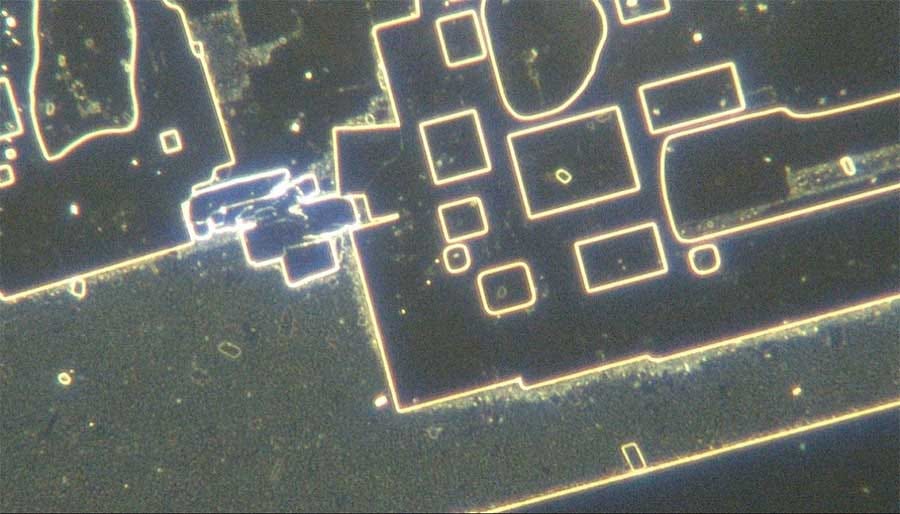

Generalmente solo después de la desecación de estas muestras o por calor pudieron observar algo verdaderamente terrorifico descrito como circuitería o algun tipo de bionanotecnología o nanotecnología que ensambla.

Este estudio recientemente publicado en Italia confirma una vez más las nanoestructuras de autoensamblaje en la sangre de personas inyectadas con C19. Los autores correlacionan los hallazgos de sangre con los síntomas del afectado. Por ejemplo, se discutió este caso:

The authors show that these self-assembly nanoparticles conglomerate to create massive structures. These provide the basis for extensive clotting and abnormal blood flow.

Here are further self assembly nanostructures:

The sudden transition, usually at the time of a second mRNA injection, from a state of perfect normalcy to a pathological one, with accompanying hemolysis, visible packing and stacking of red blood cells in conjunction with the formation of gigantic conglomerate foreign structures, some of them appearing as graphene-family super-structures, is unprecedented.

Estas 4 imágenes ilustran la variedad de fenómenos y objetos inusuales encontrados en la sangre de sujetos vacunados con Comirnaty BioNTech/Pfizer (Cortesía de Helen Krenn)MÁS

These substances, furthermore, “are visible under the dark-field microscope as distinctive and complex structures of different sizes, can only partially be explained as a result of crystallization or decomposition processes, [and] cannot be explained as contamination from the manufacturing process,” the researchers found.

Los científicos afirman que sus resultados han sido confirmados mediante las siguientes técnicas de medición: “Microscopía electrónica de barrido (SEM), Espectroscopía de rayos X de dispersión de energía (EDX), Espectroscopía de masas (MS), Análisis de plasma acoplado inductivamente (ICP), Bright Field Microscopy (BFM), Dark Field Microscopy (DFM) y Live Blood Image Diagnostics, así como análisis de imágenes mediante Inteligencia Artificial”.